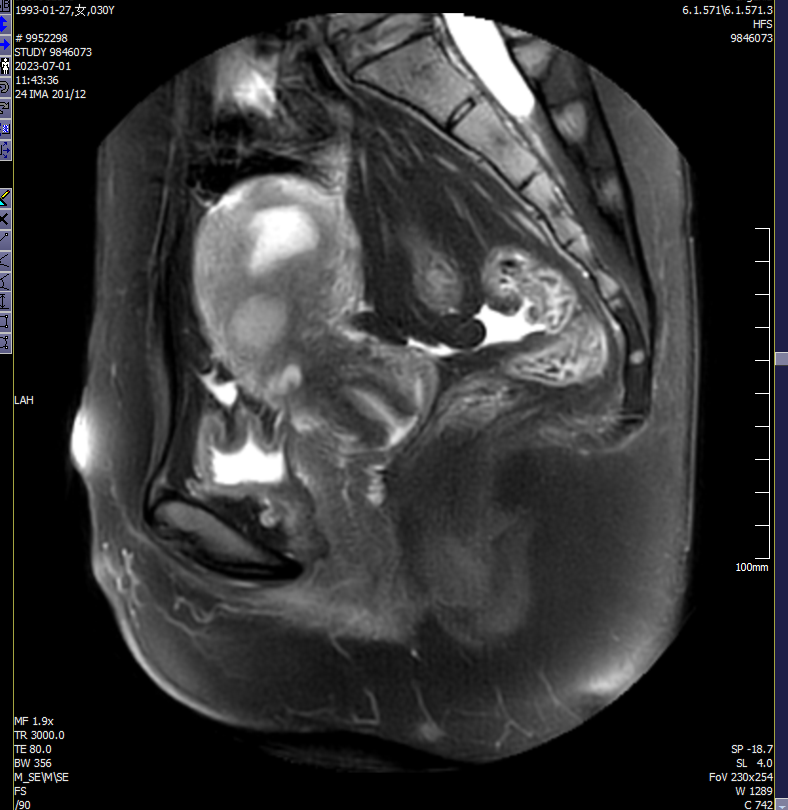

✦当超声检查无法明确妊娠囊与子宫及其周围器官的关系时,可进行MRI检查。MRI检查矢状面及横断面的T1、T2加权连续扫描均能清晰地显示子宫前壁下段内的妊娠囊与子宫及其周围器官的关系。

病史简介

患者,女,30岁,停经40余天,发现瘢痕妊娠1天。

平素月经规律,初潮13岁,6/28-30天,量中,色暗红,白带正常。LMP:2023年5月20日。

G5P2,于2016年、2020年分别行剖宫产1次,2021、2022年分别因个人意愿行药流1次。

辅助检查:

外院2023-6-29行B超提示:瘢痕妊娠6周,妊囊距肌瘤位置较近;宫内实质性占位,考虑肌瘤;左侧卵巢内等回声,建议随诊。

诊断:子宫瘢痕妊娠Ⅱ型

治疗:腹腔镜下子宫瘢痕切除术